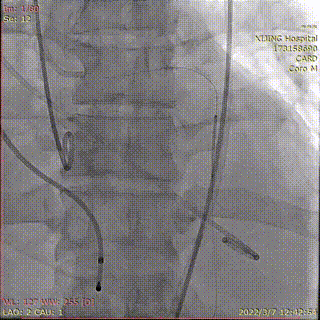

冠脉支架置于左主干并造影

完全释放Venus-A Plus

烟囱支架扩张释放

造影显示左冠通畅

术后造影显示瓣膜位置理想,冠脉充盈正常